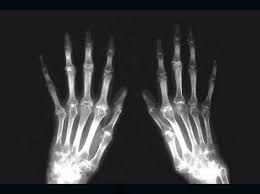

Resultado de imagen de síndrome de marfanPrincipalmente esta enfermedad se caracteriza por una estructura corporal alta y delgada: extremidades largas y delgadas (dolicostenomelia); dedos largos, como de araña (aracnodactilia); tórax en embudo o tórax en quilla; escoliosis (curvatura en la columna vertebral); defectos de la vista; pie plano; cara estrecha y delgada; micrognatia (mandíbula pequeña); coloboma del iris; hipotonía. El síndrome de Marfan se debe a defectos presentes en un gen llamado fibrilina-1, que está implicado en la producción de fibrilina, una proteína necesaria para la formación del tejido conectivo, que cuando es escasa o defectuosa provoca el debilitamiento de este tejido. Es una de cada 10.000 personas la que padece esta enfermedad y  está catalogada como una de las enfermedades más raras hasta hoy día conocidas. Se trata de una enfermedad hereditaria autosómica dominante, por lo tanto hablamos de una enfermedad que tiene la misma probabilidad de aparecer en un sexo que en otro.